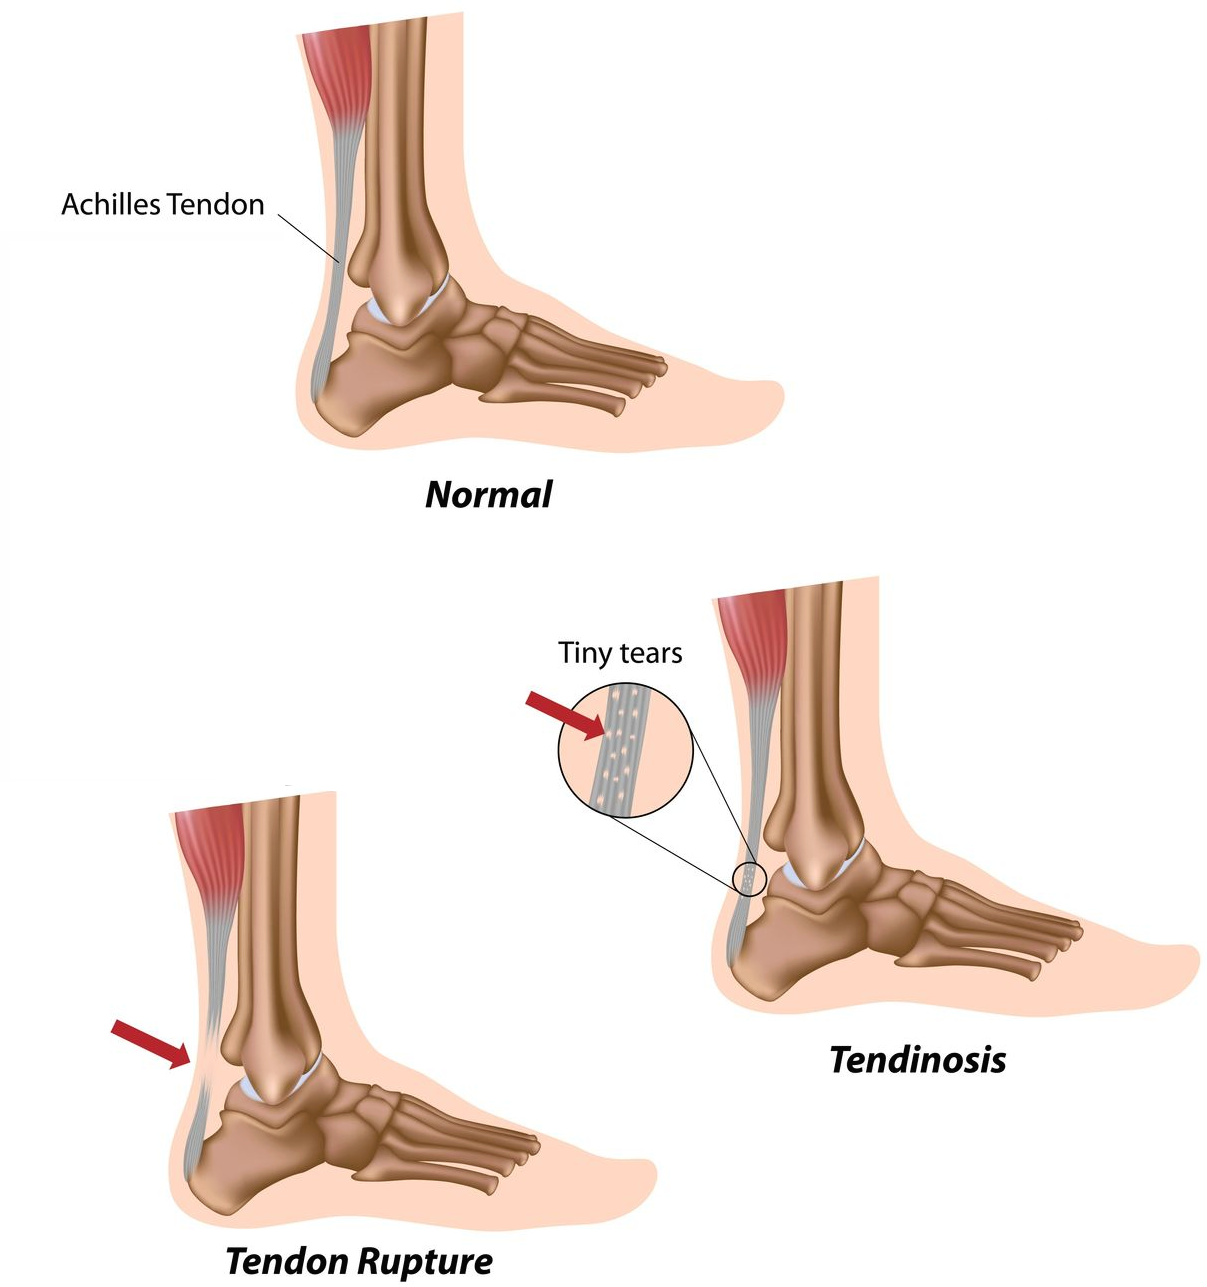

Achilles Tendinopathy (Tendinitis and Tendinosis) – Complete Feet …

Achilles Tendonitis / Tendonosis

Achilles Tendon Rupture – FootEducation